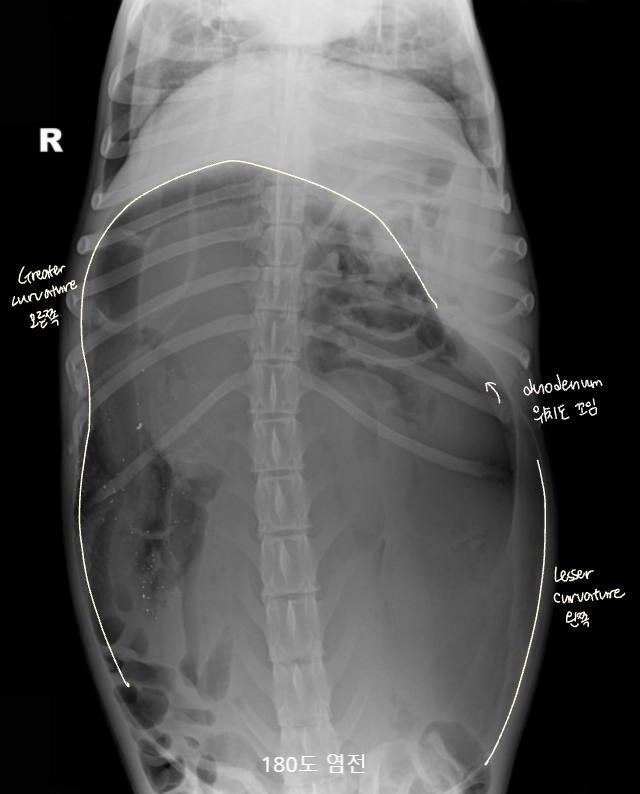

| GD | GDV | |

| VD | - greater curvature ์ผ์ชฝ(์ ์) * 360๋ ํ์ ์์๋ ์ผ์ชฝ์ ์์น | - greater curvature ์ค๋ฅธ์ชฝ (180๋ ์ผ์ ) - duodenum ์์น๋ ํจ๊ป ๊ผฌ์ |

| RL | - pylorus๊ฐ ์๋์ชฝ(์ ์) | - pylorus ์์ชฝ - ์์ ๋ถํํ(compartmentalization) : ๋ถ๋ฐฉ ํ์ธ - gastric band (soft tissue) ๊ด์ฐฐ |

![]() ![]() | ![]() ![]() | |